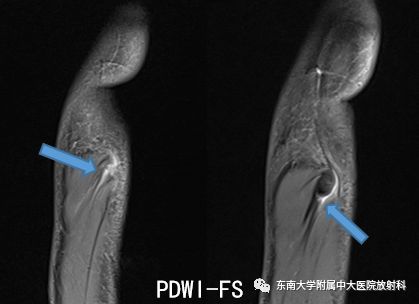

骨关节炎是一种慢性关节疾病,主要表现为关节软骨的退行性变和关节边缘骨赘的形成。这种疾病常见于中老年人,尤其是负重关节,如膝关节、髋关节等。骨关节炎的症状包括关节疼痛、僵硬、肿胀和活动受限。治疗骨关节炎的方法包括药物治疗、物理治疗和手术治疗。